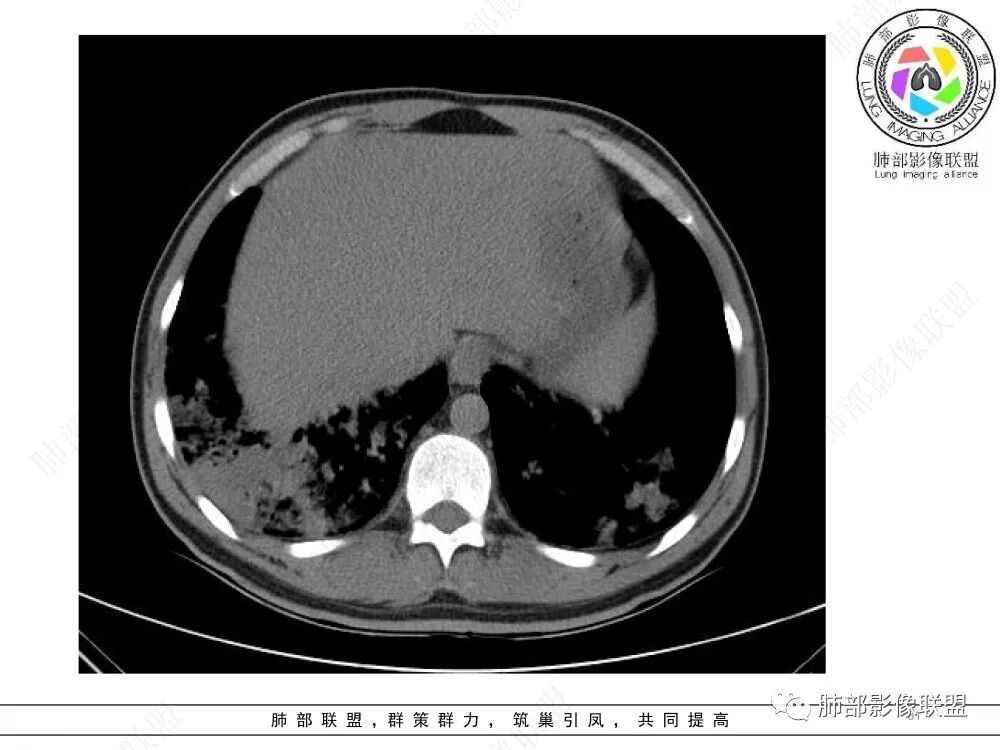

中年男性,慢性咳嗽,有吸烟史,胸部CT基础尚可,双肺多发的沿支气管播散的树芽影以及支气管管壁的增厚和对应区域内的斑片影实变影,符合气道播散的表现。经过对症抗感染治疗1月之后,胸部CT影像进展。右侧播散到左侧。实变和漱牙以及气管壁增厚均较前明显进展。

2.胸部CT:两肺广泛的支扩,支气管壁增厚,多发的树芽影,部分伴有支气管周围的渗出,少量实变。不足一月复查,原有支扩、支气管壁增厚基础上伴有大量渗出,实变,结节,胸膜下累及。

3.综合分析:首先病灶沿支气管分布,呈树芽征及实变影,相应支气管壁广泛增厚,其次病变范围比较广泛,几乎累及所有叶段,这种表现常高度提示气道播散,经过对症抗感染治疗20多天后,胸部CT影像明显进展。符合IPA的进展表现。